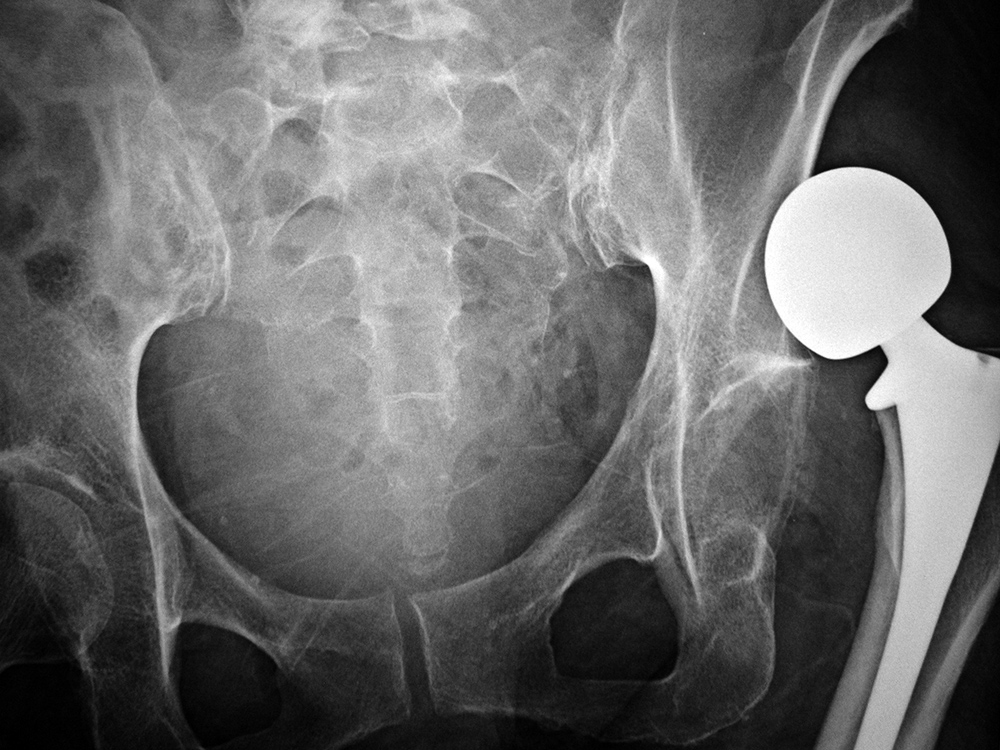

68 year-old woman with left hip metal-on-metal prosthesis. Bony erosions (arrows) are evident on the greater and lesser trochanter from probable metallosis with pseudotumor formation. |